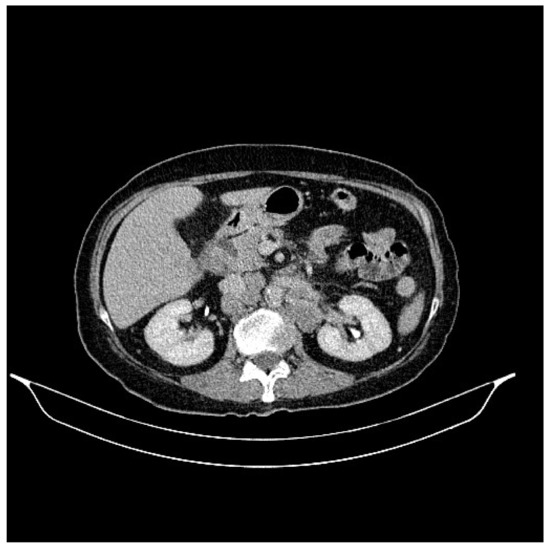

2. Case Presentation